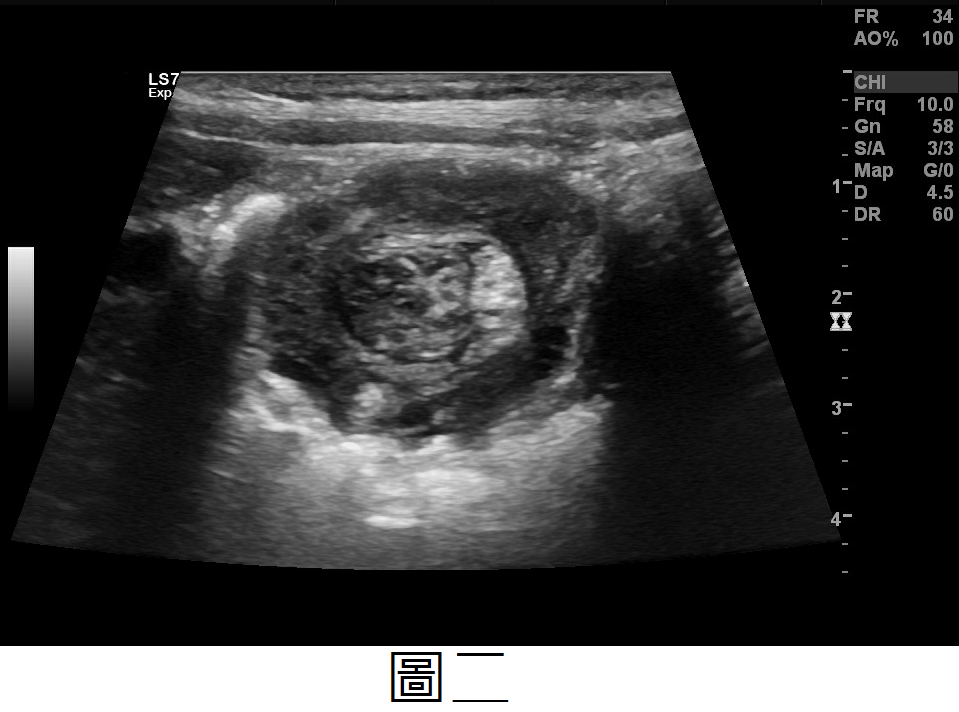

詳解

本題的關鍵在於辨識9個月大男嬰的典型臨床表現(陣發性哭鬧、嘔吐)以及腹部超音波上特徵性的「甜甜圈徵象」(target sign),這些都指向腸套疊(Intussusception)。